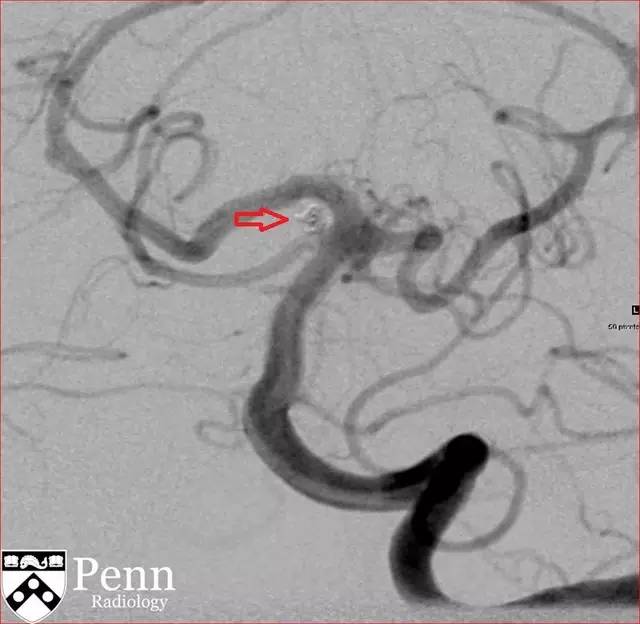

图 7 动脉瘤栓塞术后 DSA,可见动脉瘤内无对比剂充盈(红色箭头)

图 8 动脉瘤栓塞术后 DSA,可见动脉瘤内无对比剂充盈(红色箭头)

使用单个 1.5 x 2 cm 的纳米线圈对动脉瘤进行栓塞后随访 CT。